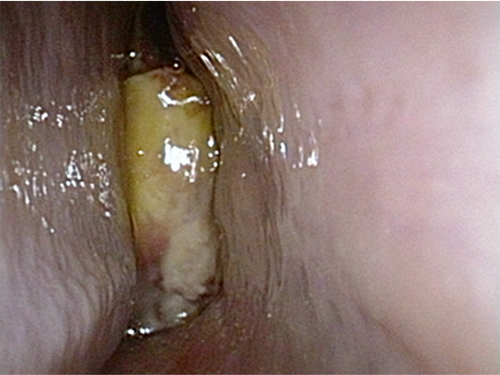

扁桃周囲膿瘍

細菌感染症による急性咽頭・扁桃炎が重症化して起こります。

アメリカのワシントン大統領の死亡した病気と言われています。

自覚的には激しいのどの痛み、嚥下痛、摂食障害や発熱・口臭などであり

治療が遅れると死にいたります。

治療は溜まった膿の排膿と抗生剤の点滴治療です。

![]() 左扁桃周囲膿瘍 咽頭全体に発赤・浮腫があり |